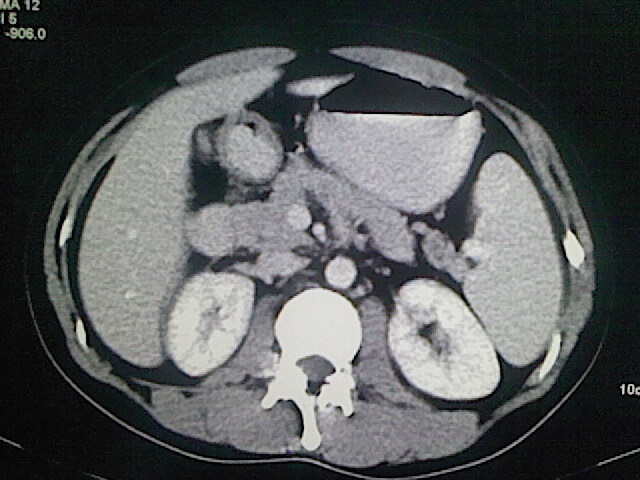

以下是引用卜一在2009-3-14 9:49:00的发言:[br]胆囊萎缩,胆囊壁不规则增厚,内部结构模糊,增强明显强化。另:肝左叶外侧段肝囊肿。支持:慢性胆囊炎!高度可疑:胆囊癌!

以下是引用余辉在2009-3-14 8:48:00的发言:[br]1)慢性胆囊炎。2)肝左叶外侧段肝囊肿。3)脂肪肝。[br]支持,胆囊萎缩,密度增高,不知b超具体有何提示,钙胆汁?结石?

以下是引用jiangjing在2009-3-14 10:18:00的发言:[br]1)慢性胆囊炎。2)肝左叶外侧段肝囊肿。3)脂肪肝。4.】建议行肝功能检查